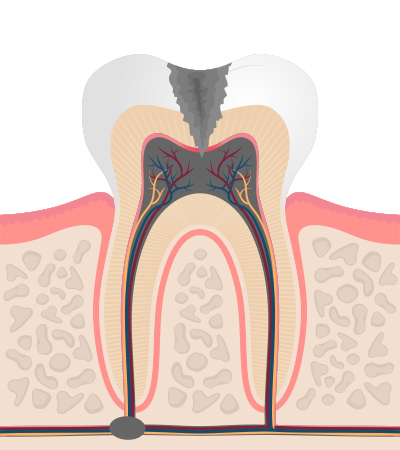

충치의 단계 및 치료법

1단계

법량질까지 진행 증상은 거의 없음